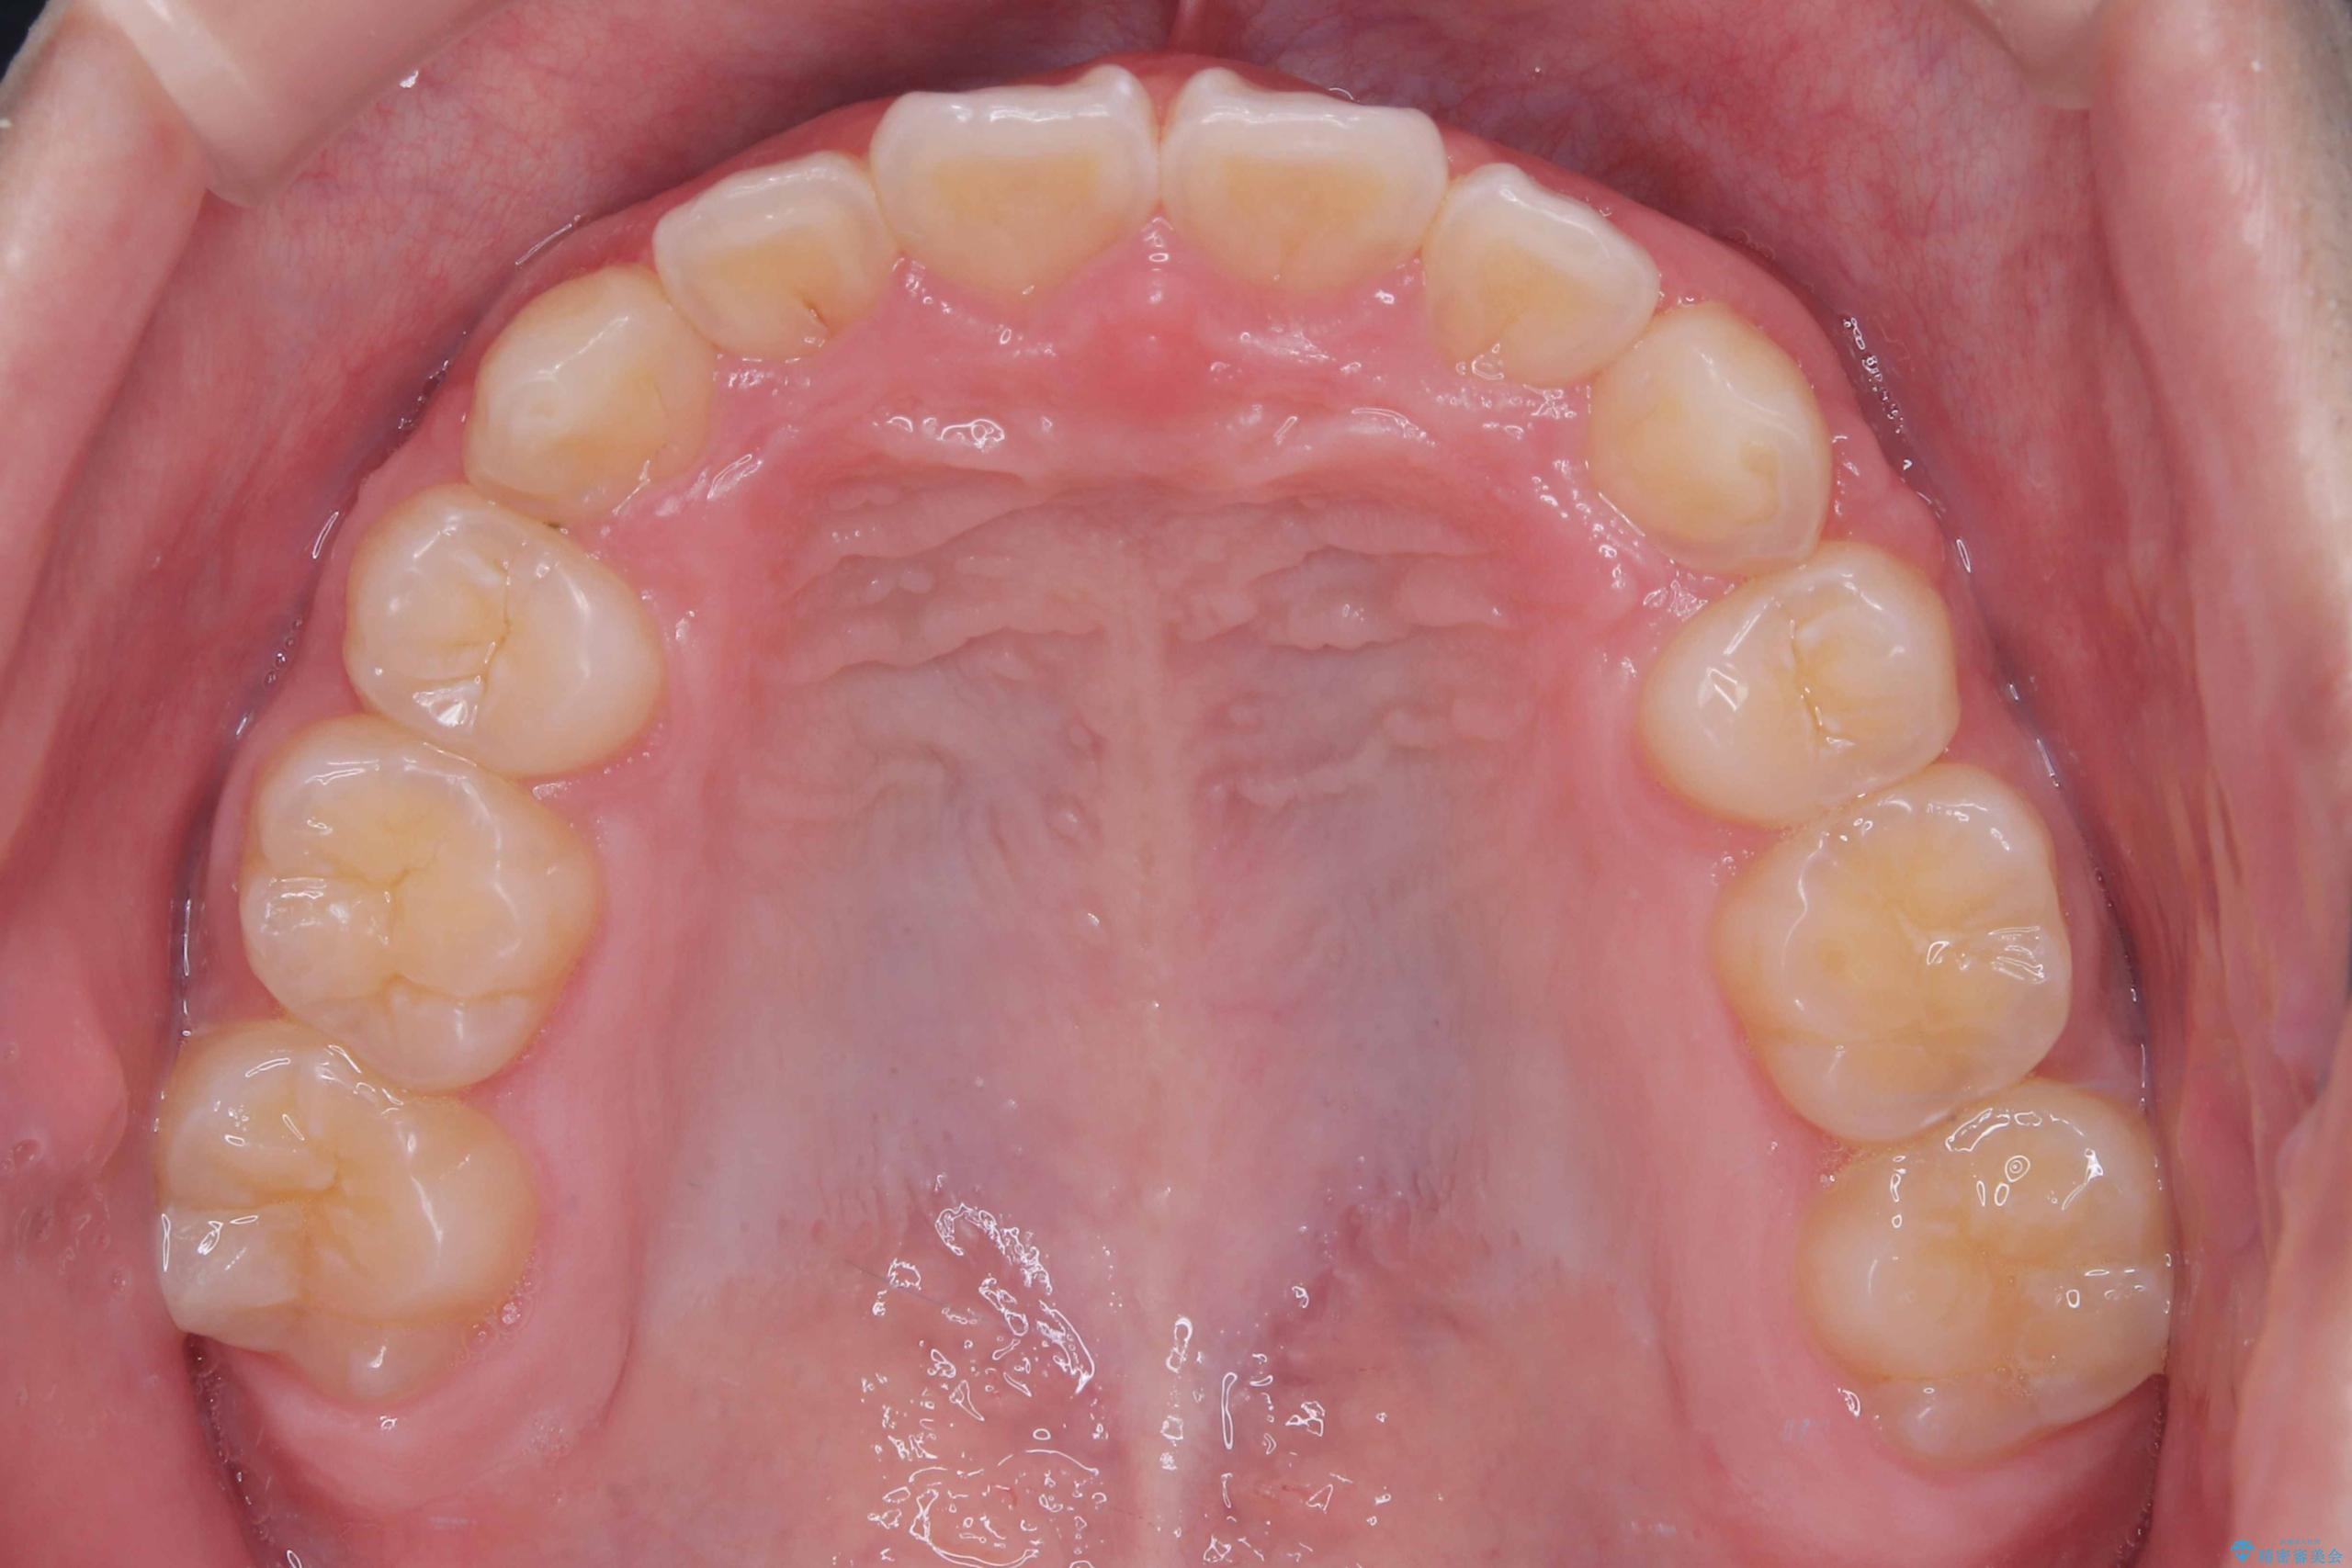

矯正の精密検査の結果上顎左右4番の計2本を抜歯し、審美性に配慮したワイヤー矯正装置(審美装置)を用いて治療を行いました。

八重歯などの歯列のデコボコが綺麗に改善され、患者様にも大変喜んでいただけました。また、咬み合わせが深い「ディープバイト」も併せて改善し、見た目だけでなく機能面でもバランスの取れた咬合を獲得しています。